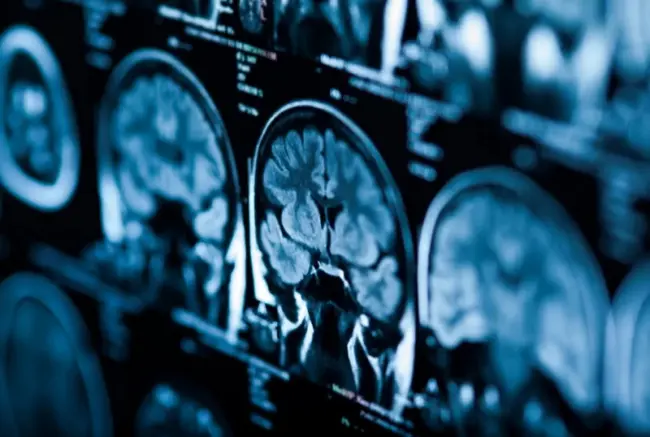

Trong khi nhiều người nghĩ rằng máy đọc ý nghĩ AI (AI thought reader) có thể yêu cầu phải cấy một thiết bị vào đầu người dùng, bước đột phá này chỉ yêu cầu dữ liệu quét fMRI (functional magnetic resonance imaging, chụp cộng hưởng từ chức năng). Theo Tiến sĩ Huth và các đồng nghiệp của ông, AI có thể giải mã dữ liệu từ quá trình quét fMRI và sau đó chia sẻ dữ liệu đó với độ chính xác cao.

AI đang phát triển nhanh chóng, đó là sự thật và thiết bị đọc suy nghĩ mới này chỉ là một ví dụ khác về tốc độ phát triển của nó. Càng thú vị hơn khi bạn hiểu được những hạn chế mà hệ thống AI này có thể vượt qua. Một điều khó khăn với dữ liệu fMRI là nó luôn khó diễn giải theo thời gian thực.

Đó là do cách fMRI đo hoạt động của não. Tuy nhiên, với những tiến bộ đạt được trong AI, chẳng hạn như nền tảng của Chat GPT-4, các nhà khoa học đã có thể huấn luyện hệ thống giải mã phản ứng của não đối với một số từ nhất định. Điều này cho phép trình đọc suy nghĩ AI hoạt động chính xác hơn.